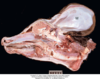

What is this?

Schistosomus reflexus - rare and fatal congenital disorder